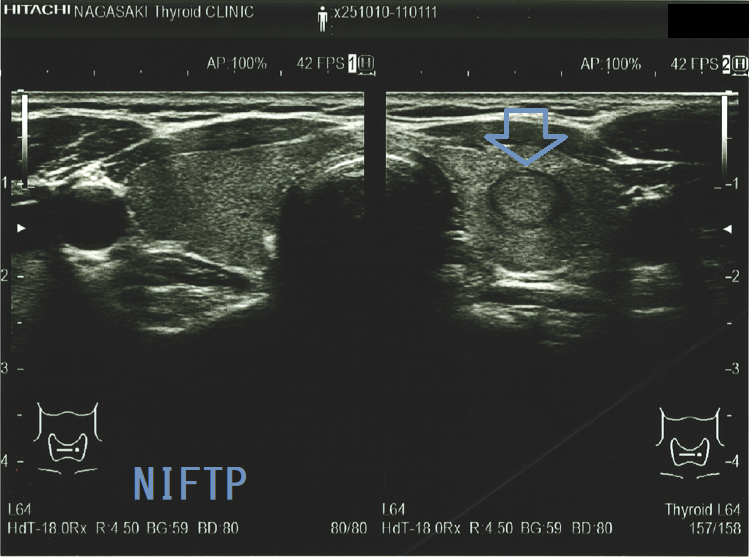

Non-invasive follicular thyroid neoplasm with papillary-like nuclear features (NIFTP) 超音波(エコー)画像;見かけは濾胞型甲状腺乳頭癌、 濾胞性腫瘍、腺腫様結節と鑑別できまない

Non-invasive follicular thyroid neoplasm with papillary-like nuclear features (NIFTP) 超音波(エコー)画像 (水平断)

Non-invasive follicular thyroid neoplasm with papillary-like nuclear features (NIFTP)の超音波(エコー)所見は、

- 被膜が存在(被膜のない場合もある)

- 充実性、等エコーが多い

- 砂粒状石灰化を認めない

などで、濾胞型甲状腺乳頭癌、濾胞性腫瘍(良性濾胞腺腫 、甲状腺濾胞癌)と鑑別できません。砂粒状石灰化のない濾胞型甲状腺乳頭癌なんて普通に存在します。NIFTPの60.1%は悪性を疑う所見が無いとされます[Endocrine. 2021 Jul;73(1):131-140.]。